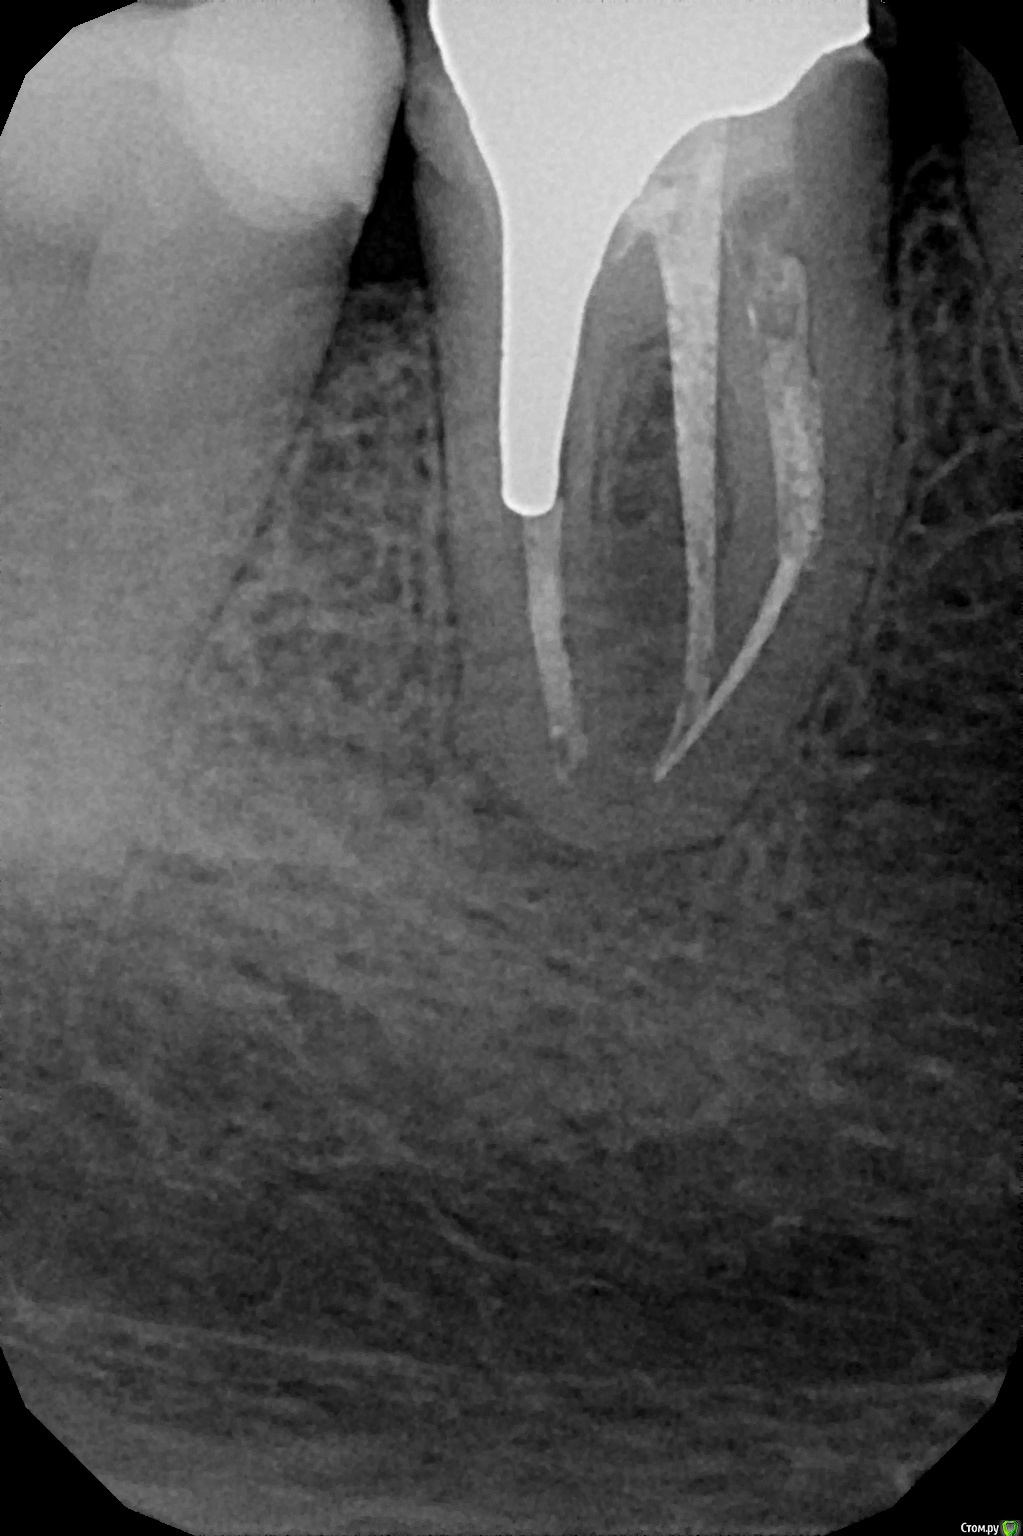

apex007 Опубликовано 22 апреля, 2016 Поделиться Опубликовано 22 апреля, 2016 Добрый вечер! Перелечивали каналы в резорциновом 46 из-за образования небольшой кистогранулемы в апикальной части. Корни у апекса изогнутые в сторону вертикальной оси зуба, поэтому пройти каналы полностью (до апекса) не удалось. Каналы закрыты гуттаперчей. Врач предлагает установить культевую вкладку, но отказывается делать рентген. Разве не нужно делать контрольные снимки в таком случае? Или здесь по принципу "уже ничего не сделать, поэтому и смысла нет"? КТ до лечения есть, могу выложить.Спасибо! Ссылка на комментарий

apex007 Опубликовано 27 января, 2021 Автор Поделиться Опубликовано 27 января, 2021 Всем ответившим большое спасибо за помощь, для истории выкладываю снимки до перелечивания () и через 4 месяца (улучшение, ). Ссылка на комментарий